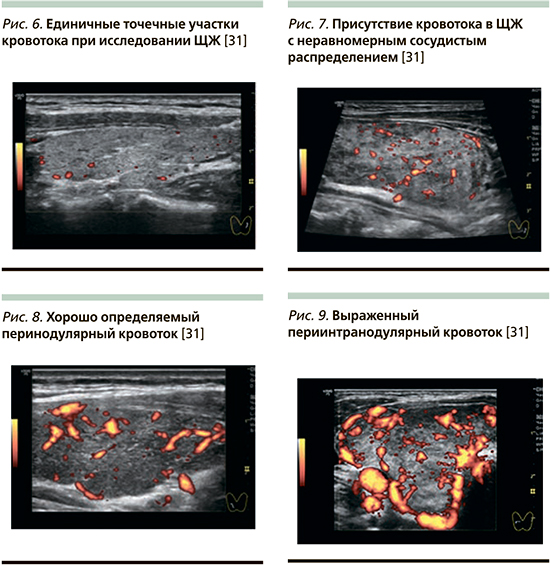

Целесообразно применение следующего протокола диагностики различных типов АмИТ по ЦДК.

«Образец 0» – отсутствие васкуляризации или единичные точечные участки кровотока при исследовании ЩЖ (рис. 6) [32].

«Образец I» – присутствие кровотока в ЩЖ c неравномерным сосудистым распределением или васкуляризацией внутри узла (рис. 7) [32].

«Образец II» – небольшое усиление кровотока с неравномерной васкуляризацией или хорошо определяемый перинодулярный кровоток (рис. 8) [32].

«Образец III» – значительное усиление васкуляризации с однородным кровотоком или выраженный периинтранодулярный кровоток (рис. 9) [32].

При исследовании пациентов с АмИТ при 1-м типе определялись образцы I–III, при 2-м – 0 [2]. Вместе с тем диагностика смешанного варианта АмИТ с помощью ЦДК невозможна. По результатам шести различных исследований чувствительность и специфичность ЦДК для дифференциальной диагностики 1-го и 2-го типов АмИТ составили соответственно 96,8–93,6% и 94,1–90,1% [24, 27, 30].